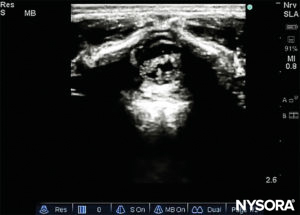

The probe is positioned first in a transverse plane at the sacrum level; this is called the short-axis view (SAX). The exact position of the cornua and the sacrococcygeal membrane (SCM) are defined (Figure 4). With the sacrococcygeal membrane in the middle of the image (Figure 5), the probe is then rotated 90 degrees into a midline sagittal position over the lower sacrum, which is called the long-axis view (LAX; Figure 6). The SCM and the ventral and dorsal layer of the os sacrum, with the caudal epidural space in between, are easily identified. In small children, the dural sac may be visible in this position, although in older children you need to scan more in a more cephalad direction (Figure 7). These movements can be performed in the opposite order, but a complete exploration of the space in both axes is recommended.

The needle insertion angle is noted during the scan. The needle may be advanced 2–4 mm into the caudal space, and the stylet is removed. To ensure optimal caudal placement of the needle, a small bolus of saline or local anesthetic is administered under US guidance with the probe in the midline (LAX; Figure 10). The probe is positioned as cephalic as needed to visualize the dural sac in the US screen (Figure 11). When the injection starts, you will notice the dura being displaced ventrally, especially in younger children. The spread of local anesthetic can be monitored by moving the probe cephalic up the spine in the midline or in a paramedian sagittal axis (Figure 12). The same dura movement can be visualized with the probe in the SAX in the more cephalic positions (Figures 13 and 14).